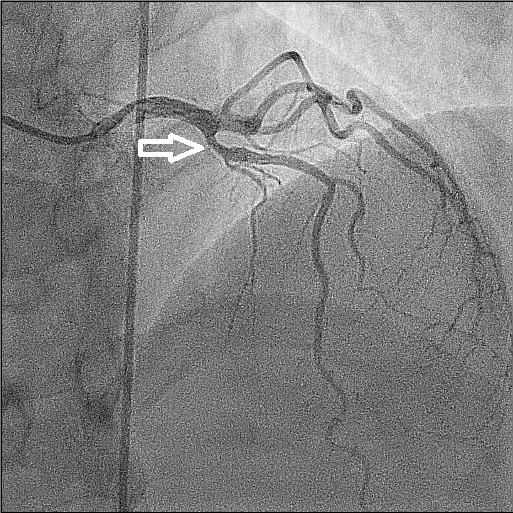

Figuur 2 – Linkerkransslagader (LCA) vóór toediening nitroglycerine intracoronair.

Witte pijl geeft de locatie aan waar de spasme zich bevindt.